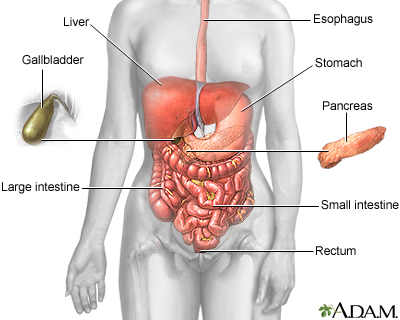

Crohn disease is a disease where parts of the digestive tract become inflamed.

- It most often involves the lower end of the small intestine and the beginning of the large intestine.

- It may also occur in any part of the digestive system from the mouth to the end of the rectum (anus).

Crohn disease is a form of inflammatory bowel disease (IBD).